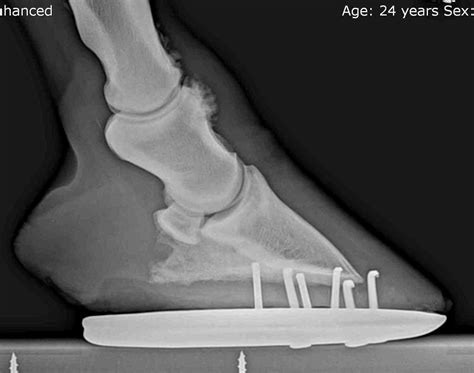

• Imaging: Radiographs (X-rays) are often used to visualize the bony growths and assess the extent of the damage. In some cases, ultrasound or MRI may be recommended for a more detailed view.

• pictures of ringbone in horses